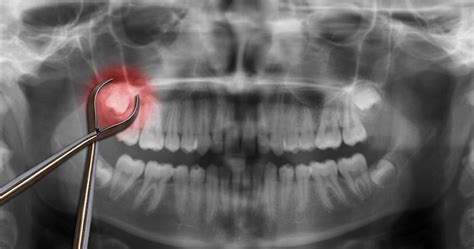

Undergoing a dental extraction is a common procedure, yet the period immediately following the surgery is critical for your recovery. The most vital component of this healing process is the formation and preservation of an after extraction blood clot. This clot acts as a natural bandage over the empty socket, protecting the underlying bone and nerve endings while facilitating the growth of new tissue. If this clot is dislodged or dissolves prematurely, you risk developing a painful condition known as dry socket. Understanding how to protect this clot is essential for a smooth, pain-free recovery.

Following the removal of a tooth, your body immediately triggers a clotting response to stop bleeding. This gelatinous mass is the foundation of your recovery. Without it, the jawbone remains exposed to the oral environment, leading to intense pain that can radiate to your ear, eye, or temple. Protecting the after extraction blood clot is not just about comfort; it is about preventing infection and ensuring the healing progresses at the intended pace.

• Visible bone: If you can see white bone in the socket instead of a dark clot or healing tissue.